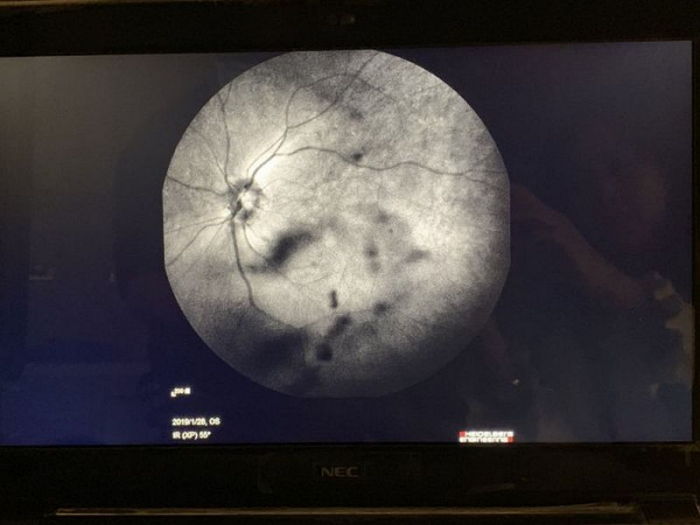

検査の結果、少年は眼球に早期老化が進行していることで、白内障まで生じた状態であったことが分かりました。

これにより、スマホの画面で発生するブルーライトに過度に露出されてしまい、水晶体に悪影響を及ぼした結果、白内障にかかったとのことでした。